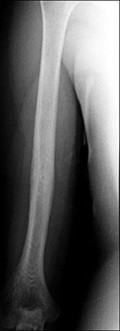

A 32-year-old male develops extreme pain out of proportion, pain with passive stretch, and tense compartments following a closed tibial shaft fracture. Which of the following best describes the fundamental pathophysiologic mechanism leading to cellular hypoxia and tissue death in acute compartment syndrome?

Explanation

The pathophysiology of compartment syndrome is driven by an increase in interstitial tissue pressure within a closed non-yielding fascial space. As tissue pressure rises, it quickly surpasses the low capillary venous pressure, severely impairing venous outflow. This leads to a decreased arteriovenous (AV) pressure gradient, resulting in diminished local capillary blood flow, capillary collapse, ischemia, and subsequent muscle/nerve necrosis. Arterial inflow is typically maintained until very late, which is why pulses are usually palpable even in established compartment syndrome.